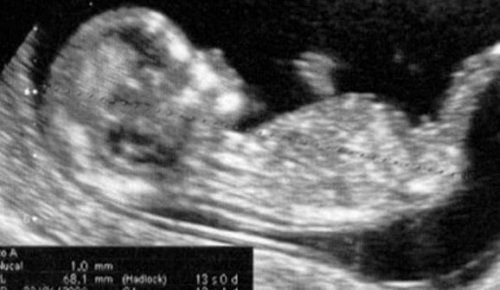

I den 13. uge af graviditeten kan ultralydet til slutningen af første trimester stadig udføres, hvis det ikke allerede er gjort.

Dette er det sidste skridt i serien af kontrolundersøgelser, som moderen skal have, da graviditeten først blev bekræftet.

Dette er det punkt, hvor evalueringen af første trimester afsluttes.

Der kan siges, at den sværeste og foruroligende del allerede er forbi, især for nye mødre.

Mediciniske check-ups bliver mindre hyppige, men kun i en kort periode.

Månedlige check-ups er nødvendige for at sikre, at fostret udvikler sig korrekt, og selvfølgelig, at moderen heller ikke lider nogen form for ubehag.